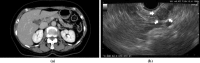

Accumulated evidence has revealed that endoscopic ultrasonography (EUS) has had a great impact on the clinical evaluation of pancreatic cancers. EUS can provide high-resolution images of the pancreas with a quality regarded as far surpassing that achieved on transabdominal ultrasound (US), computed tomography (CT), or magnetic resonance imaging (MRI). EUS is particularly useful for the detection of small pancreatic lesions, while EUS and its related techniques such as contrast-enhanced EUS (CE-EUS), EUS elastography, and EUS-guided fine needle aspiration (EUS-FNA) are also useful in the differential diagnosis of solid or cystic pancreatic lesions and the staging (T-staging, N-staging, and M-staging) of pancreatic cancers. In the diagnosis of pancreatic lesions, CE-EUS and EUS elastography play a complementary role to conventional EUS. When sampling is performed using EUS-FNA, CE-EUS and EUS elastography provide information on the target lesions. Thus, conventional EUS, CE-EUS, EUS elastography, and EUS-FNA are essential in the clinical investigation of pancreatic cancer.